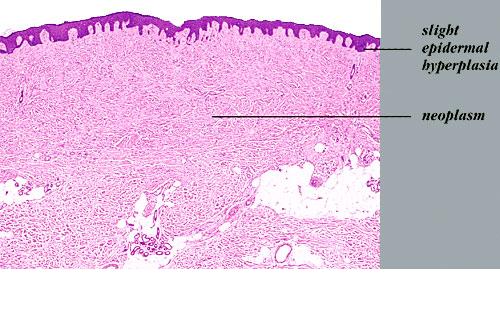

Dermoid_cyst =كيسة جلدانية Dermoid Cyst Dermoid cysts are subcutaneous cysts that usually are present at birth. They occur most commonly on the head, mainly around the eyes, and occasionally on the neck. When located on the head, they often are adherent to the periosteum. Usually they measure between 1 and 4 em in diameter. Histopathology. Dermoid […]